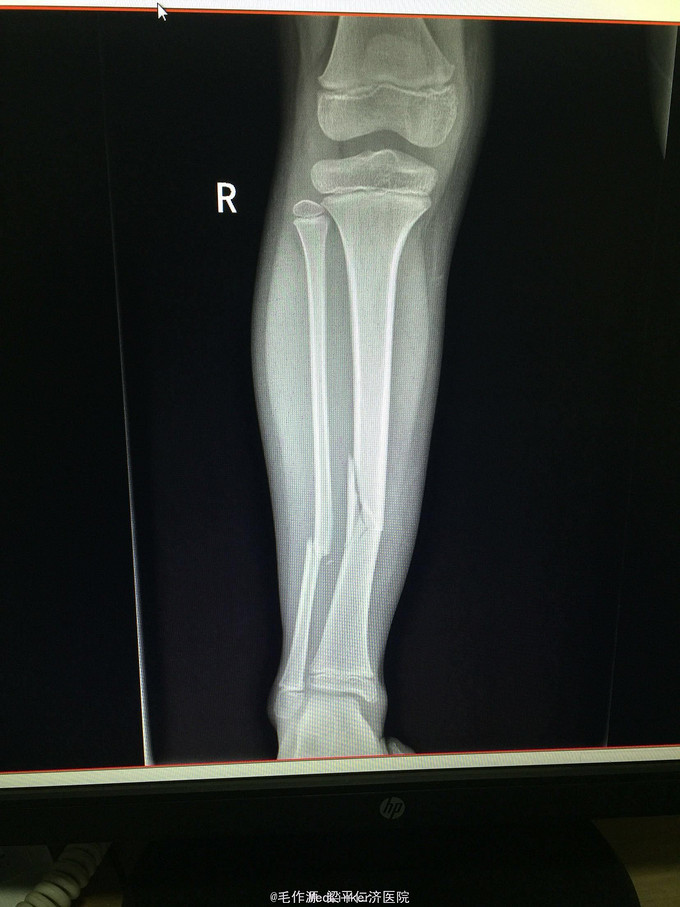

右下肢肿胀、畸形,局部压痛明显,可扪及骨擦感及骨擦音,轴向扣痛(+),有假关节活动,右足背动脉可扪及,肢体远端血供及感觉正常。 右下肢DR正侧位示:右胫腓骨中下段骨折。

1、右胫腓骨中下段骨折(R)

骨折移位明显,有手术指征,准备完善相关术前检查,若无特殊手术禁忌症,拟于近日行“右胫腓骨骨折切开复位内固定术”。